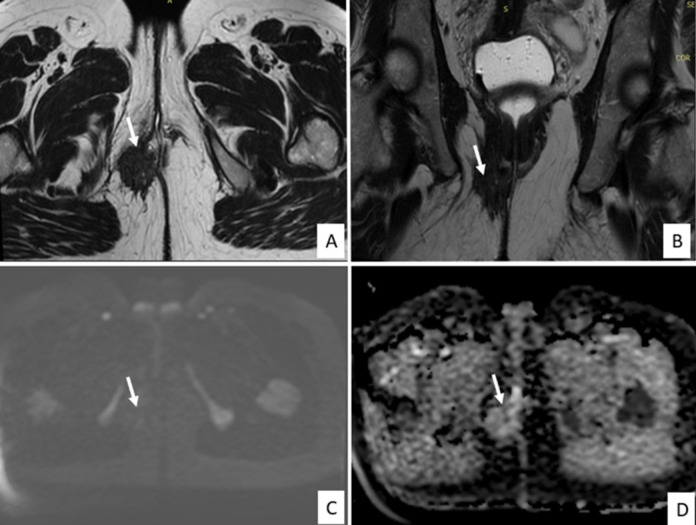

子宫内膜异位症是一种慢性非癌性妇科疾病,通常见于育龄妇女。它描述了子宫内膜腔外存在功能性子宫内膜成分、腺体和间质,最常涉及卵巢、腹膜和子宫韧带等盆腔结构。会阴子宫内膜异位症是一种罕见的盆腔外子宫内膜异位症,估计发病率在0.3%至1%之间。我们报告了一例36岁的孕妇,妊娠1段(G1P1),有阴道分娩史,没有子宫内膜异位症的病史,在接受会阴中外侧切开术两年后,出现了位于右侧会阴疤痕的疼痛肿块。肿块与周期性疼痛和生活质量明显受损有关。临床检查,结合超声和磁共振成像(MRI),建议在没有其他子宫内膜异位症病变的情况下诊断会阴子宫内膜异位症。由于患者拒绝手术,开始激素治疗,在8个月的随访中症状明显改善。虽然没有获得组织学证实,但典型的临床表现,令人回味的MRI特征以及对激素治疗的良好反应支持会阴子宫内膜异位症的诊断。在会阴切开术后出现周期性会阴疼痛的育龄妇女中,应系统地考虑这一未被充分认识的实体。

Endometriosis is a chronic, non-cancerous gynecological disorder that is typically observed in women of fertile age. It describes the presence of functional endometrial components, glands and stroma outside the endometrial cavity, most often involving pelvic structures such as the ovaries, peritoneum, and uterine ligaments. Perineal endometriosis is a rare form of extrapelvic endometriosis, with an estimated incidence of between 0.3% and 1%. We report the case of a 36-year-old woman, gravida 1 para 1(G1P1), with a history of vaginal delivery and no known history of endometriosis, who presented with a painful mass located on the right perineal scar two years after undergoing a mediolateral episiotomy. The mass was associated with cyclical pain and significantly impaired quality of life. Clinical examination, combined with ultrasound and Magnetic Resonance Imaging (MRI), suggested the diagnosis of perineal endometriosis in the absence of other endometriotic lesions. As the patient declined surgery, hormonal therapy was initiated, resulting in marked symptom improvement at 8-month follow-up. Although histological confirmation was not obtained, the typical clinical presentation, evocative MRI features, and favorable response to hormonal therapy supported the diagnosis of perineal endometriosis. This under-recognized entity should be systematically considered in women of reproductive age presenting with cyclical perineal pain following episiotomy.